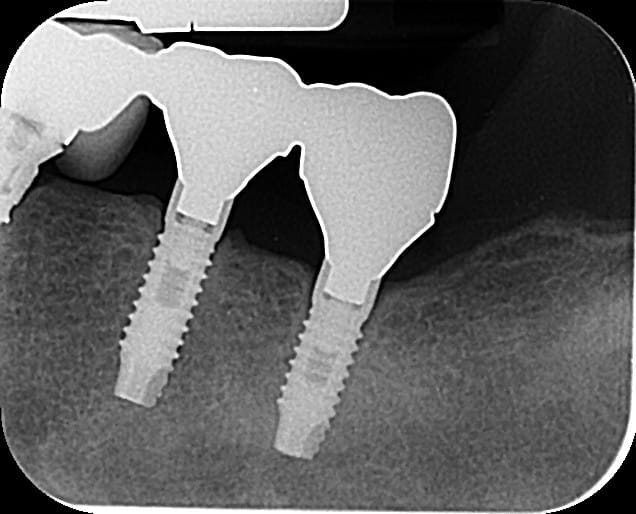

Pouvez-vous m'aider, je n'arrive pas à identifier la marque des implants 36/37. C'est ni du ZIMMER, ni du MIS.

Ci-joint la rétroalvéolaire

SWEDEN MARTINA

https://www.spotimplant.com/fr/implants-dentaire/sweden-martina/pro-link-in-link